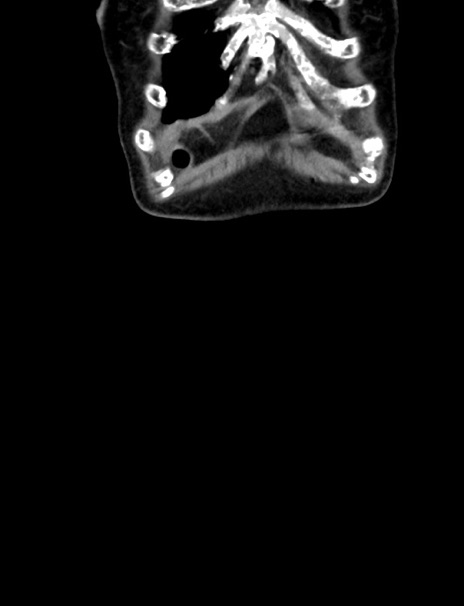

症例33(冠状断像)

【症例】70歳代 女性

【主訴】心窩部痛

【現病歴】延髄病変の精査・加療にて神経内科入院中。本日より心窩部痛あり。

【身体所見】右下腹部を中心に圧痛と反跳痛あり。

【データ】WBC 10900、CRP 0.02